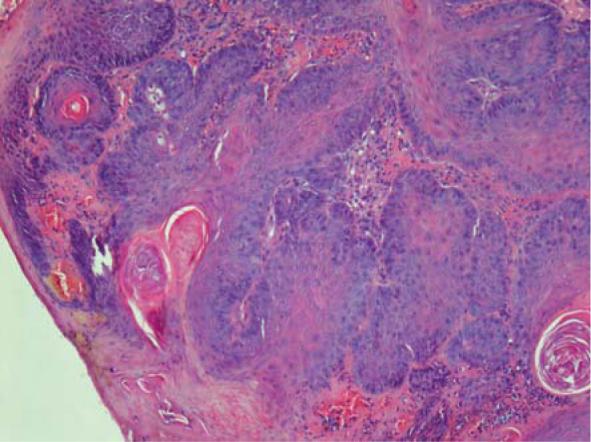

Mast cell tumour, sebaceous gland adenoma, and less common squamous papilloma are skin tumours in ferrets (), and early excisional surgery is usually the treatment of choice. The aim of our study was to investigate the effectiveness of electrochemotherapy (ECT), a new, minimally invasive non-surgical method, as first treatment option of different types of ferret skin tumours located on surgically difficult sites.

A 5-year-old castrated male ferret with two cutaneous masses, presenting 4 months apart and a 7-year-old spayed female ferret with two cutaneous masses, that appeared simultaneously on two locations are presented. In the first patient, both masses were diagnosed as mast cell tumours, and in the second patient, squamous papilloma and sebaceous adenoma were diagnosed. One session of ECT with bleomycin injected intratumourally was applied in all tumours.

肥大细胞瘤、皮脂腺腺瘤以及较少见的鳞状乳头瘤是雪貂的皮肤肿瘤(),早期切除手术通常是首选治疗方法。我们研究的目的是调查电化学疗法(ECT)这种新的、微创的非手术方法,作为位于手术困难部位的不同类型雪貂皮肤肿瘤的首选治疗方案的有效性。

介绍了一只5岁去势雄性雪貂,有两个皮肤肿物,相隔4个月出现;以及一只7岁绝育雌性雪貂,有两个皮肤肿物,同时出现在两个部位。在第一只雪貂中,两个肿物均被诊断为肥大细胞瘤,在第二只雪貂中,诊断为鳞状乳头瘤和皮脂腺腺瘤。所有肿瘤均采用瘤内注射博来霉素进行了一次ECT治疗。